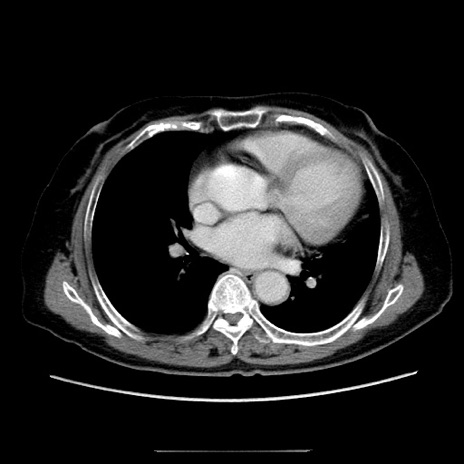

症例5(横断像)

【症例】70歳代女性

【主訴】お腹が張る

【現病歴】1週間くらい前から腹部膨満の自覚あり。昨日夜から増悪したため、本日救急外来受診。

【身体所見】意識清明、BT 36.5℃、BP 165/106mmHg、HR 80bpm、SpO2 98%、腹部:膨満、軟、自発痛・圧痛なし、触診にて不快感あり、腸蠕動音:減弱

【データ】WBC 12600、CRP 1.04